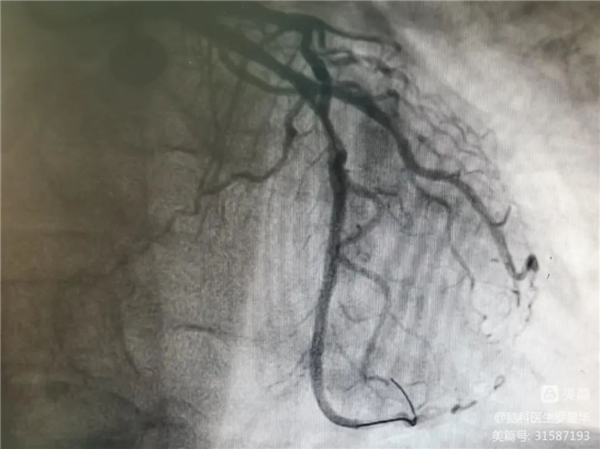

支架植入后狹窄完全解除

沈桂冬主任團隊正在為患者行PCI術